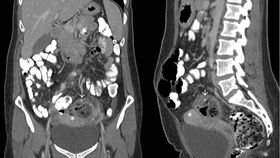

The rest of this article is behind a paywall. Please sign in or subscribe to access the full content.The 32-year-old woman was first admitted to hospital in Rochester, Michigan, with stomach pains, and a preliminary scan revealed evidence of a possible colon abscess. However, further investigation revealed that her left ovary had become enlarged to 6.7 by 5 centimeters (2.64 by 2 inches) – more than double its normal size.

The ovary was firmly stuck to the wall of the pelvis and the colon, and had to be surgically peeled away. Next to the ovary was a large cyst called a dermoid, which the study authors describe as “very foul-smelling [and] suspected of superinfection.”